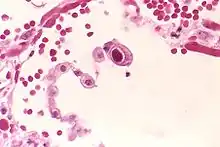

| CMV infection of a human lung pneumocyte | |

CMV infection can be demonstrated microscopically by the detection of intranuclear inclusion bodies. On H&E staining, the inclusion bodies stain dark pink and are called "owl's eye" inclusion bodies.[45]

Lytically replicating viruses disrupt the cytoskeleton, causing massive cell enlargement, which is the source of the virus' name.